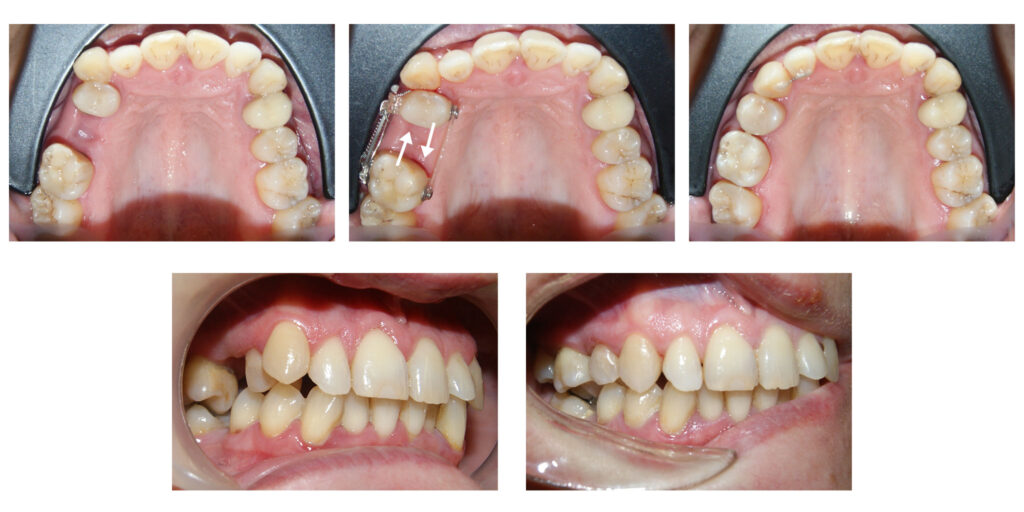

Extruzia ortodontică a dinților cu distrucție subgingivală accentuată salvează unii dinți de la extracție…pentru că dintele natural este cel mai bun implant. Săgețile evidențiază cât de multă extruzie am reușit să obținem în câteva luni.